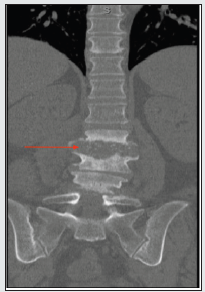

A 57-year-old female with a past medical history of chronic back pain and severe L3-L5 spinal stenosis, presented to the emergency department with acute-on-chronic lower back pain. The patient’s medical history also included newly diagnosed hepatitis C virus infection, alcoholic fatty liver disease, polysubstance abuse, alcohol use disorder, COPD, and hypertension. The patient reported an extensive history of lower back pain that was progressively worsening over the past several weeks. Physical examination was significant for paravertebral tenderness, reduced range of motion and ambulation secondary to pain, and clonus of the bilateral lower extremities. No neurological deficits were found on the exam. On presentation, the patient had mild leukocytosis, but laboratory results were otherwise unremarkable. Imaging performed in the ED was suggestive of discitis and osteomyelitis of the L2-L3 lumbar spine (Figure. 1). Neurosurgery evaluated the patient and did not recommend surgical intervention at that time. Magnetic resonance imaging (MRI) of the lumbar spine revealed inflammatory changes of discitis osteomyelitis at the level of L2-L3, with signs of early osteomyelitis at L4-L5 (Figures. 2 & 3). A bone biopsy of the lumbar spine and aspiration of the intervertebral disc was performed by Interventional Radiology. Although the bone biopsy was negative for organisms, cultures of the aspiration from the intervertebral disc was positive for Parvimonas micra. Blood cultures showed no growth to date. Upon additional questioning, the patient reported having a toothache for the past several weeks and was not able to seek proper dental care. Further investigation of the oral cavity identified a right upper molar infection. During admission, the patient was treated with intravenous vancomycin and ceftriaxone. She was then transitioned to two weeks of oral ampicillinsulbactam, followed by an additional two weeks of oral amoxicillin and clavulanic acid to ensure complete clearance of the infection. The patient showed improvements in mobility and pain and was stable for discharge after 12 days of hospitalization.